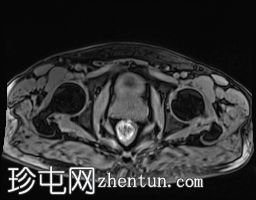

轴位

DWI

DWI/ADC:高b值DWI呈弥漫性高信号,ADC呈相应低信号(扩散受限)。评分5/5。

DCE:早期强化阳性。

PI-RADS:5 - 极高风险(极有可能存在临床意义的癌症),考虑炎症性病变。

肉芽肿性前列腺炎是多参数磁共振成像 (mpMRI) 中一种重要的、与临床意义显著的前列腺癌相似的疾病,因为它可以产生明显的周围带异常,伴有扩散受限和早期强化,通常导致较高的 PI-RADS 分级。

在本病例中,mpMRI 显示双侧周围带弥漫性 T2 低信号,高 b 值 DWI/ADC 图像上呈扩散受限,早期强化阳性,并伴有包膜轮廓隆起。这种影像学表现可能类似于浸润性或广泛性周围带癌,尤其是在 PSA 升高和直肠指检异常的情况下。然而,炎症性疾病,特别是肉芽肿性前列腺炎,可能出现类似的影像学表现。经直肠前列腺活检的组织病理学检查显示,患者患有严重的慢性非干酪性肉芽肿性前列腺炎,未见肿瘤证据。